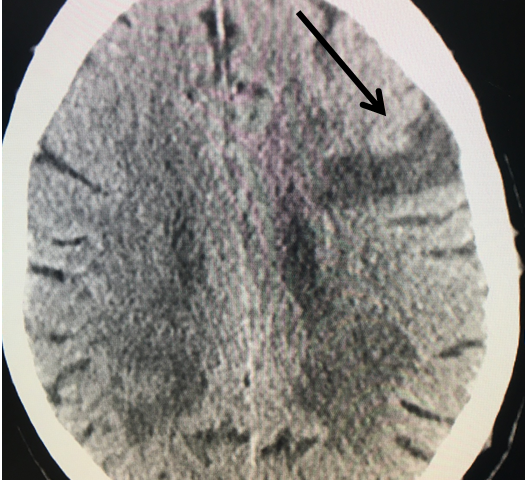

Figure 2.

Catheter angiography prior to angioplasty revealed critical stenosis (Figure 2). Angioplasty was therefore performed under local anesthesia with an embolic protection device deployed to catch any dislodged debris (Figure 3). After angioplasty, a stent was opened across the lesion to maintain long-term patency (Figure 4). Post-stent angiography showed smooth dilatation of the lesion. The patient’s aphasia continued to improve at his 6-week follow-up visit and duplex revealed no significant stenosis through the stent.